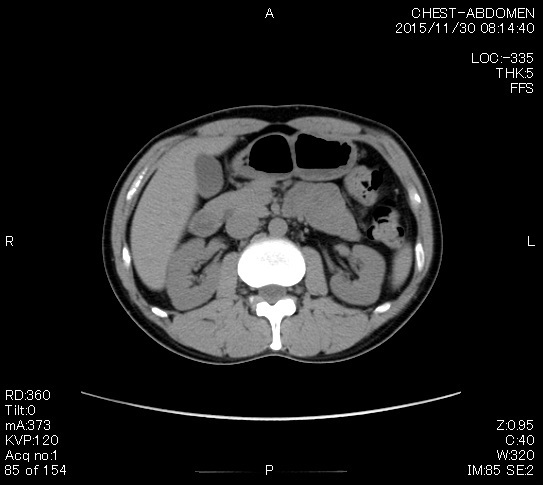

2006年入院治療の退院日から10年。 かなり大きな節目なんだが、なんだろうこの軽い感じは(笑)。 「10年生きたんだぁ」くらい。 変わったような変わっていないような。 当時は10年後なんて全く考えていなかった。 今も10年後は考えていないが・・・。 退院前日の2006/10/31は46.6kgだった。 今日計ったら54.8kg。体脂肪は16.6%。 とても健康にストレスなく生活できていることに、治療当時から現在に至るまで、関わった人全員に感謝の気持ちです。 マーカー、CT画像、問題なし!! 血液検査結果もほとんど文句なしの正常値。 そうだなぁ、数値に出ない異変としては、肩凝りかなぁ。 一旦夏になくなったと思ったが、初秋から再発。 マウスを左手にしたり、シップ貼ったり、最近はホッカイロ貼ったり。 で、一向に良くなる気配がない。 やはり四十肩なのか。 でも肩の可動域は問題ない。動かせないような痛みも無い。 結局色々考えてたどり着いたのは「変形性頚椎症」ではないかと。 肩凝りや頭痛がダラダラと続くようになるという症状がピッタリ当てはまる。 さて、改善策がなかなか難しい。 整形外科行ってもレントゲン撮って湿布をくれるだけだろう。 そんなことに大金を出すならまずは300円/回のプールで泳ごうと思う。 重力から開放して全身運動をするのが一番良いらしい。 2015年の目標は少しでも良いから水泳を再開する、だな。 マーカー、CT画像、問題なし!! 通常の血液検査結果も文句なしの正常値がズラ~っと並んだ!! 間違いなくヨメの食事のおかげである。ほんとうに感謝である!! ちなみに最近少々腰周りの肉付きが気になっていたのだが・・・。 左から2013年12月、2013年06月、2012年12月と背骨の位置は合わせて並べてみた。 6月まではあまり変化がなかったが、この半年で明らかに違う。 背中側の脂肪がやや増えてはいる。 でも最も大きな違いは、腸なのか、やたらと内臓が膨れている・・・。 一言で言うと食べすぎ?!?! 食事は野菜中心ではあるが、確かによく食べているw。 せっかくスーツのウエストを詰めたんだからこれ以上にならないようにしたい。 「腹八分目を心がける」かな。